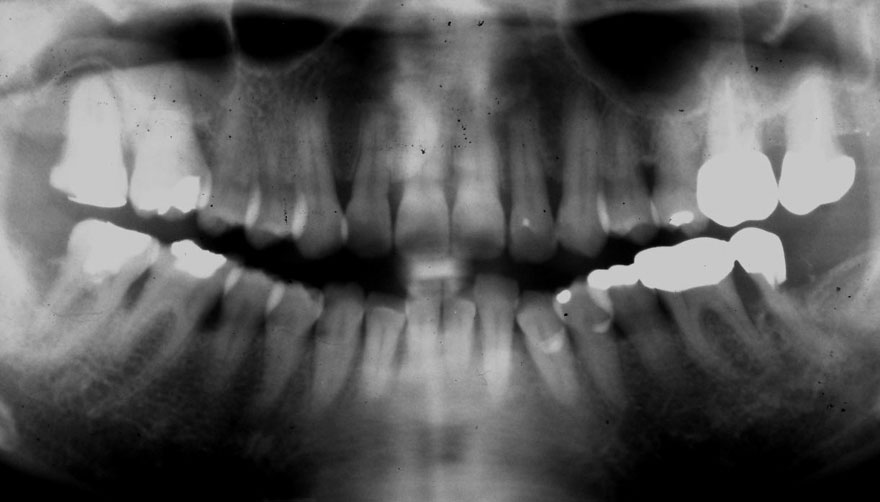

初診時 40歳 女性 平均歯槽骨喪失量:5.24mm

20年後 60歳

平均歯槽骨喪失量:5.79mm

21年間喪失量:-0.55mm

年間喪失速度:-0.027mm

(ケア頻度:1.23ヵ月ごと)